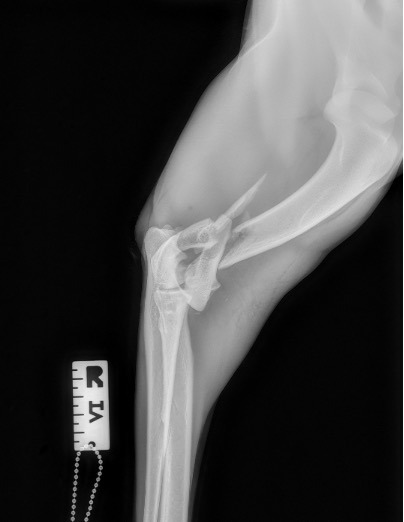

Exemple 1 :

Figure 1 : Pré-op